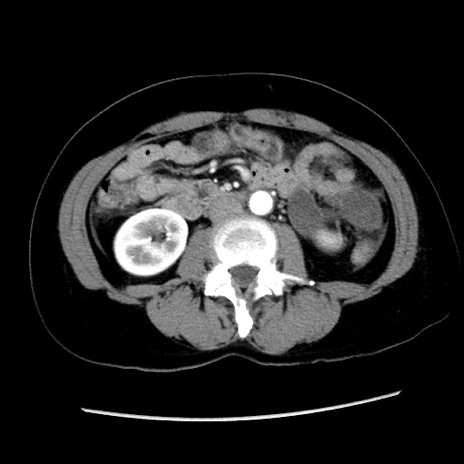

症例10(横断像)

【症例】 50歳代女性

【主訴】 腹痛

【現病歴】前日生レバーを食べた。今朝に排便あり。 昼前に突然発症の腹痛を生じ、当院救急外来を受診した。

【既往歴】 子宮筋腫にてで子宮全摘後

【身体所見】 意識清明、腹部:平坦、軟、下腹部やや左を中心に圧痛・反跳痛あり、筋性防御あり

【データ】WBC 7800、CRP 0.07